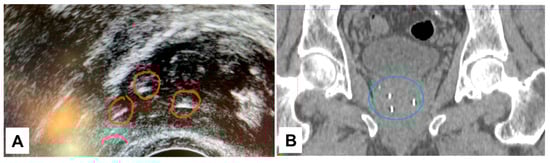

3.4. Visibility of NOVA Markers in a Clinical Case